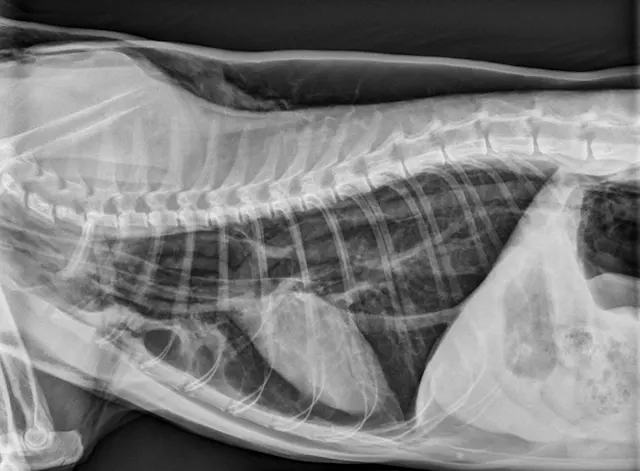

Figure 1 Radiographic image of a cat with a tracheal tear and severe subcutaneous emphysema

Radiography can be used to diagnose tracheal tears (Figures 1 and 2). If a tracheal tear is present, thoracic radiographs may reveal pneumomediastinum, subcutaneous emphysema, pneumoretroperitoneum, hyperinflated lung fields, a gas-filled pseudo-airway at the level of the rupture, focal narrowing of the tracheal lumen, and/or pneumothorax if the mediastinum has been perforated due to air pressure.3